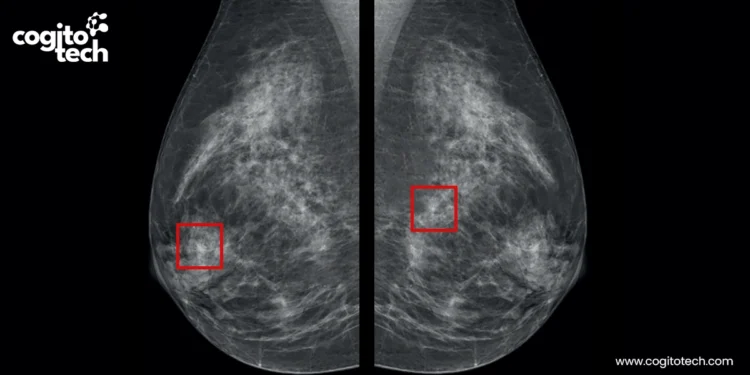

Abnormality detection and lesion scoring

Identifying and annotating tumors, lesions, and bleeding for surgical AI model training requires special attention. If a model delineates a tumor boundary incorrectly by even a few millimeters, a surgeon relying on that output may leave cancerous tissue behind or inadvertently damage a vital organ.

- Lesion localization and scoring: Precisely annotated lesion locations and severity in medical images support accurate diagnosis, disease assessment, and AI-driven surgical planning and clinical decision-making.